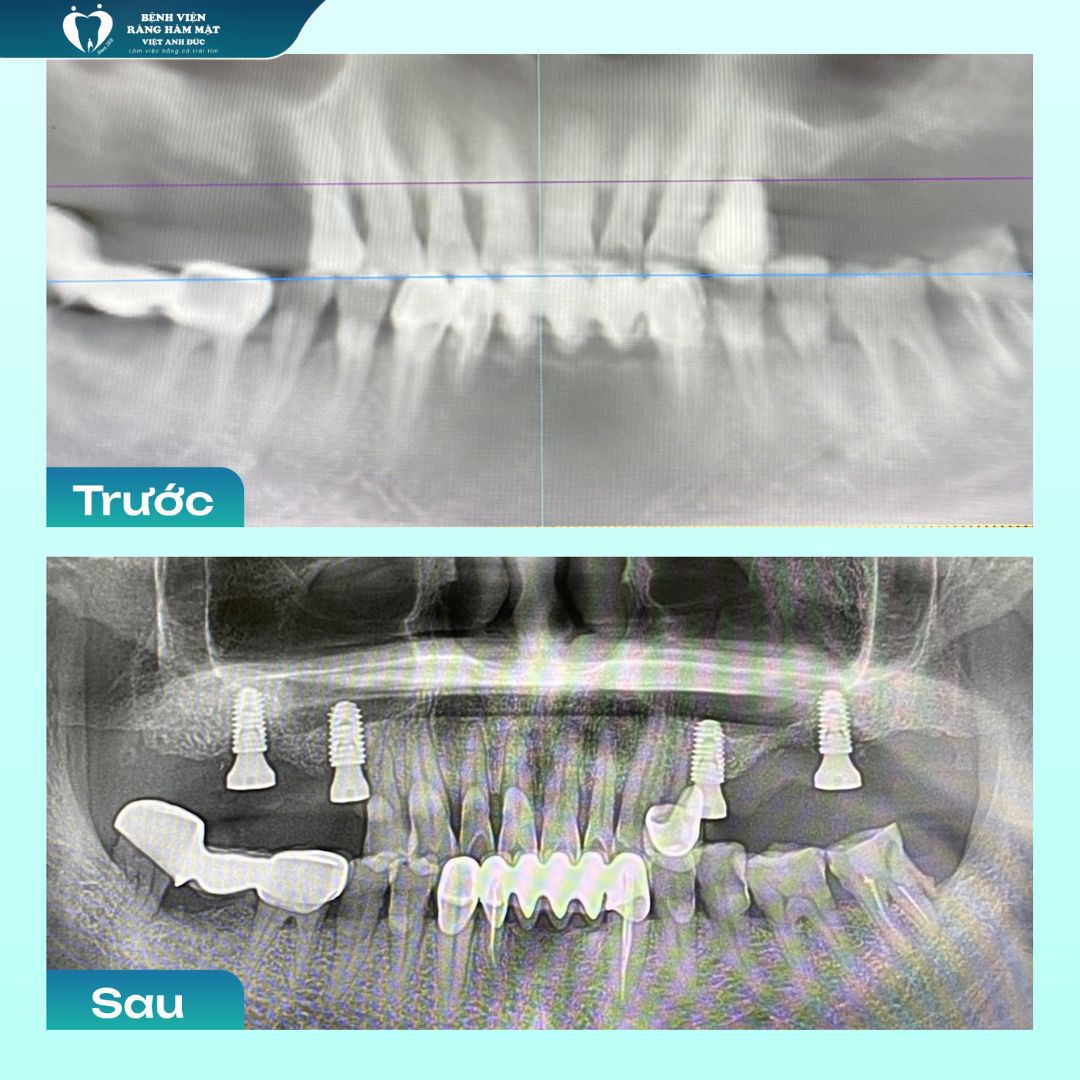

Trong suốt quá trình công tác, bác sĩ Phú đã trực tiếp thực hiện thành công hơn 3.000 ca tiểu phẫu và cấy ghép Implant, từ những ca đơn giản đến các trường hợp phức tạp cần ghép xương, nâng xoang. Với sự am hiểu sâu sắc về cấu trúc xương hàm, giải phẫu răng miệng cùng kỹ năng lâm sàng vững chắc, anh luôn đưa ra phác đồ điều trị chính xác, tối ưu cho từng bệnh nhân.

Các ca điều trị thành công bởi Bác sĩ Phú